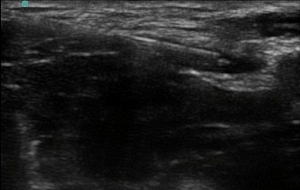

Figure 3. Needle placed into the wedge-shaped tissue space lateral to the femoral artery, lateral to the femoral nerve

- Aim to place the needle tip immediately adjacent to the lateral aspect of the femoral nerve, into the wedge-shaped tissue space lateral to the femoral artery.

- Spread should be visualised below the fascia iliaca and ideally surrounding and highlighting the nerve (“doughnut sign”).

Figure 4: Needle repositioned above the nerve, aiming to surround the femoral nerve with a “doughnut” of local anaesthetic

- Due to contrast enhancement, the hyperechoic nerve often becomes more prominent after injection of hypoechoic local anaesthetic.